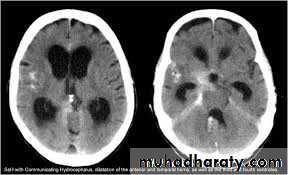

Hydrocephalous

2 types

Obstructive ( non – communicating )

Non –obstructive ( communicating )

No obstruction of the ventricular pathway , but the absorption of the csf at the level of arachnoids' granulation is occluded secondary to lodge by blood clot or inflammatory cell or infection post meningitis most commonly to occur post SAH .

CT Scane